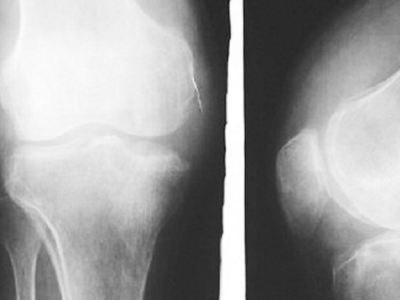

关节肿胀、疼痛比较显著,并伴有积液、骨刺、游离骨。

滑膜炎是滑膜炎症刺激所致。膝盖有大多数关节滑膜、膝关节滑膜炎很容易被见到。滑液细胞的分泌物可以润滑和营养关节,所产生的热量是因为膝关节运动的滑液和血液循环。当关节是受内部和外部因素,滑膜反应,导致拥塞或水肿,渗出的液体,表现为关节肿胀、疼痛、功能障碍。也可以说是关节积液,即滑膜炎症。